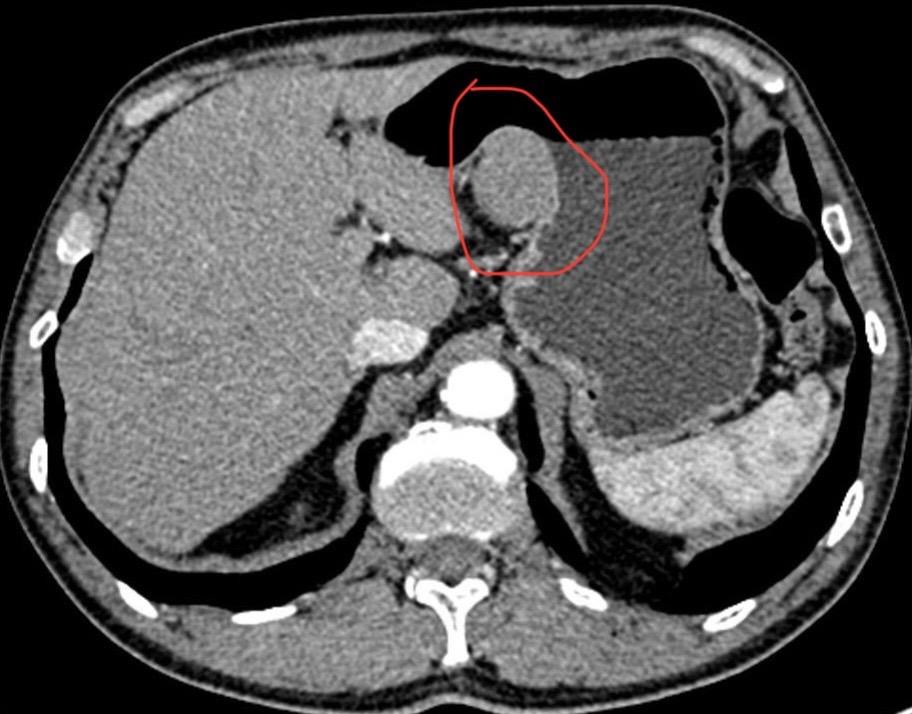

内镜医生最有成就感的事?发现早癌!这个月做了三十台四级手术,一些疑难杂症也是费力老鼻子劲了,但这些和发现早癌相比微不足道!看一个医院胃肠镜的水平,最重要的一个指标是早癌发现率!